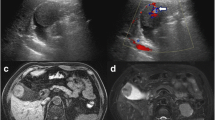

Examinations including whole body computed tomography (CT) before each surgery demonstrated no evidence of distant metastasis. A surveillance follow-up CT scan revealed a gallbladder lesion. No symptoms suggested cholecystitis, and the only biochemical abnormality was a slight elevation in levels of aspartate transaminase and alanine transaminase. Ultrasonography (US) showed a mass at the gallbladder fundus. Its surface was smooth, and the inner echo was slightly high and homogenous (Fig. 1).

A contrast-enhanced CT scan showed a 12-mm polypoid mass with high attenuation, enlarged from 4 mm 2 years ago (Fig. 2a, b). It had significantly high intensity in the arterial phase. On the coronal reconstruction image, attenuation was inhomogeneous in the mass and relatively higher on the wall side (Fig. 2c, d). There was no significant accumulation of contrast agent in any organ other than the gallbladder.

A computed tomography scan shows tumor growth from 4 mm to 12 mm over a span of 2 years (a 2 years prior, b present). A contrast-enhanced computed tomography scan shows high intensity of the tumor during the arterial phase (d yellow arrow) in comparison with plain computed tomography (c yellow arrow)